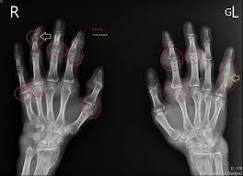

醫師觀點☀尿酸☀痛風是一種急性的關節炎,症狀包括關節紅腫、發熱、劇烈疼痛,主要發生原因是尿酸結晶累積在關節,時間久了甚至引發急性痛風性關節炎、長 ...

想說滿多人對於痛風想法都不太對,就稍微整理了痛風跟普林食物之間的關係,之所以會痛風,主要是因為尿酸堆積在關節導致白血球去攻擊這些尿酸結晶, ...